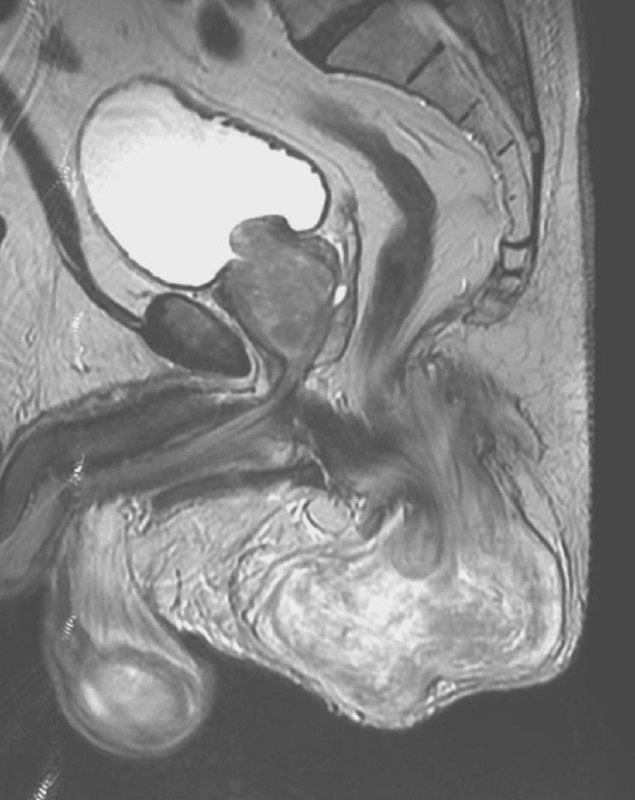

В 1691 году Антон Нук, голландский анатом, был первым, кто описал этот канал, который сейчас назван его именем. Канал Нука является женским эквивалентом вагинального отростка у мужчин, который обычно исчезает в течение первого года жизни. Он состоит из складки, выпячивания брюшины, которая прикрепляется к матке круглой связкой и проходит через паховое кольцо вдоль круглой связки в большие губы. Обычно верхняя часть этого выпячивания обтурируется во время рождения или непосредственно перед ним и исчезает в течение первого года жизни. В редких случаях эта обтурация не завершатся, что приводит к сохранению канала Нука и может вызвать образование женского гидроцеле, а именно кисты канала Нука.

Видимо, в зависимости от того, проксимально или дистально и на каком протяжении просвет канала остается открытым, такой протяженности и локализации и формируется его киста.

В нашем случае, скорее всего, киста сформировалась лишь в проксимальных отделах этого канала, а перегородки и неправильная форма могут служить признаком перенесённых травматизации или воспалений. Клинически никак не проявляется, случайно обнаружена на УЗИ, по всей видимости, потому, что не ущемляется в канале и никак снаружи не пальпируется.

А может это и лимфатическая мальформация. В любом случае, верификация вряд ли будет, но узнать о кисте канала Нука всегда полезно тем, кто о ней никогда не слышал. Пусть эта штука послужит тем замечательным поводом.